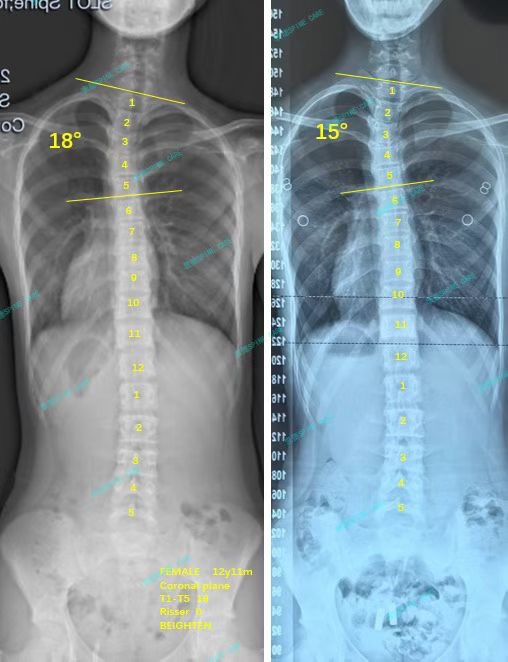

我是昕昕,坚持ZDT矫正三个月,上胸弯下降至15度,体态明显改善~

案例主人:昕昕 发现侧弯年龄:13岁 侧弯情况:Cobb角度18度

很快三个月过去了,我的上胸弯从18度降到了15度,体态也明显好了很多,我和爸爸妈妈都觉得非常值得,这三个月的努力没有白费,特别感谢杨博士和衷德团队,谢谢你们~

Soon, three months passed, and my upper chest bend dropped from 18 degrees to 15 degrees, and my posture was obviously much better. My parents and I thought it was very worthwhile. The efforts of these three months were not in vain. Special thanks to Dr. Yang and Zhongde Team, thank you ~